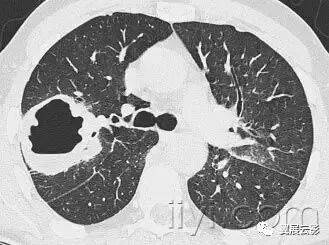

附图为小叶中心性肺气肿

十八、小叶中心性:

解剖:小叶中心性用于描述次级肺小叶的支气管血管束中心区域。病理学上也用这一术语描述终末小支气管远端,位于呼吸性细支气管和肺泡管中心的病变。

CT:正常次级肺小叶中心的点状或者线状的密度增高影,胸膜下25px范围内最明显,代表小叶内的动脉,直径约1mm。

小叶中心性异常包括(1)结节(2)树芽征,提示小气道病变(3)由于临近间质的增厚或者浸润导致小叶中心结果更加清晰(4)小叶中心性肺气肿导致的异常低密度。